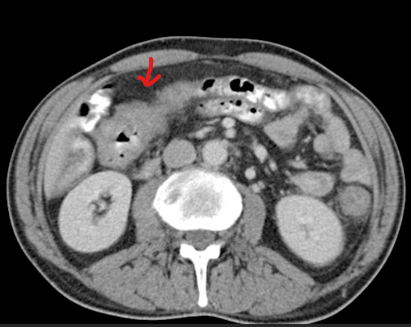

Paciente pós QT. HD?

Tiflite (enterocolite neutropênica).

Espessamento da parede do ceco, estrias na gordura pericecal , pneumatose intestinal (gás na parede intestinal) em paciente imunossuprimido.